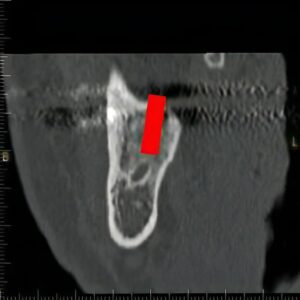

- 下歯槽神経損傷

- 下あごの場合、骨の中に神経・血管が通るスペースがあります。植え込む際にここまで穴を開けて神経を傷つけてしまうと、舌や口唇に麻痺や違和感が出ることがあります。

このステントを装着した状態で、CT撮影を行い、どこにインプラントを入れ、どのように歯を並べられるかを調べます。同時に、撮影データを使いパソコン上で手術シミュレーションを行うことにより、手術前に上記の偶発症・合併症などの手術リスクを評価していきます。